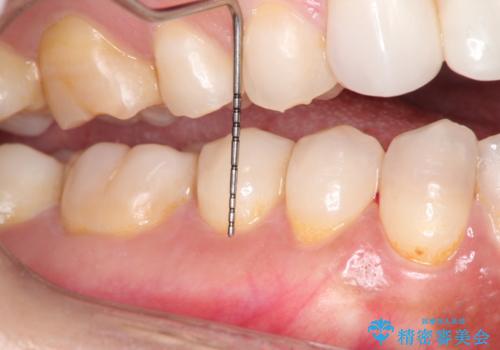

- 昔に受けた矯正治療がきっかけで歯肉が下がってしまった事を主訴として来院された患者様です。

結合組織移植術を行う方法を提案しましたが、傷口が口蓋にもできるのが嫌だとのことで、代替案としてバイオマテリアルを併用した根面被覆術を計画致しました。

治療対象部位は右下4,5,6番の3本です。